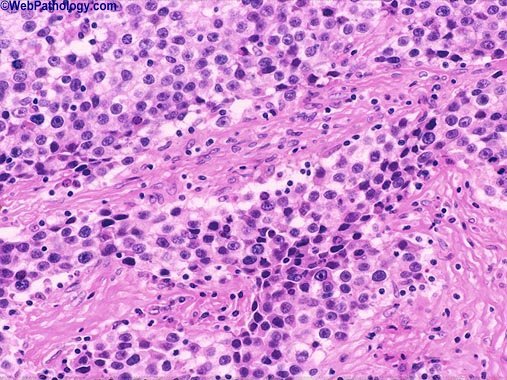

Histologic examination of cutaneous metastases from breast cancer is likely to demonstrate:

1 Dense lymphocytic infiltration

2 Tumors cells perivascularly

3 Eosinophilia

4 Tumor cells in the lymphatics

5 Band-like dermal infiltrate

Tumor cells in the lymphatics

Histologic appearance of metastatic breast carcinoma to the skin typically shows tumor cells in linear arrangement in so-called “Indian-filing” pattern. These tend to occur in the dermis and subcutaneous lymphatics. Extensive lymphatic dissemination may be caused by retrograde lymphatic spread. The tumor cells are large, pleomorphic with hyperchromatic nuclei.